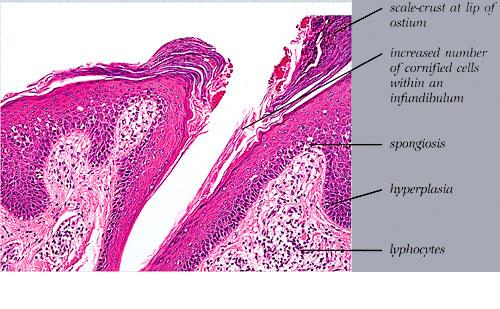

Histopathology. The histopathologic features are a combination of those observed in psoriasis and spongiotic dermatitis. Mild cases may exhibit only slight subacute spongiotic dermatitis. The stratum corneum contains focal parakeratosis, with a predilection for the follicular ostia, a finding known as shoulder parakeratosis . Occasional pyknotic neutrophils are present within parakeratotic foci {neutrophilic parakeratosis}, sometimes with fluid {neutrophilic crust}. There is moderate acanthosis with regular elongation of the rete ridges, mild spongiosis, and focal exocytosis of lymphocytes. The dermis contains a sparse mononuclear cell infiltrate. In HIV-infected patients, the epidermis contains apoptotic keratinocytes, and the dermal infiltrate usually contains plasma cells. |